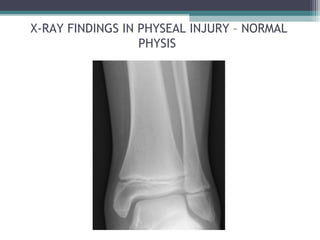

X-RAY FINDINGS IN PHYSEAL INJURY – NORMAL

PHYSIS

X-RAY FINDINGS INPHYSEAL INJURY – NORMAL PHYSIS